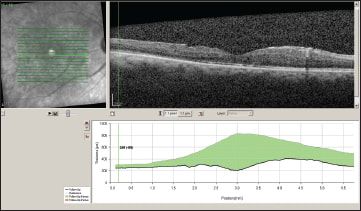

We diagnosed Birdshot chorioretinitis, and started the patient on an anti-inflammatory regimen that included 60 mg of oral prednisone daily as well as periocular injection of triamcinolone acetonide OU. However, there was no significant improvement in visual acuity or CME (Figure 2).

Figure 2. Left eye (top image) and right eye (bottom image) six weeks after starting systemic and periocular therapy.